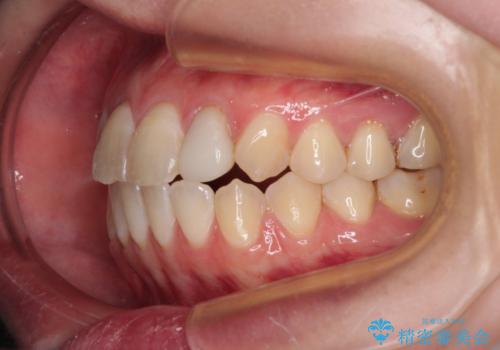

開咬を治す インビザラインによる矯正治療

- 上下前歯の開咬を気にして来院された患者様です。

開咬はインビザラインを用いると有意に改善ができるため、インビザラインによる矯正治療を行うこととしました。

途中1年8ヶ月ほど来院されず、久しぶりの来院後は治療が面倒とのことで、前歯の叢生や隙間に不十分な点が残った状態での終了となりました。